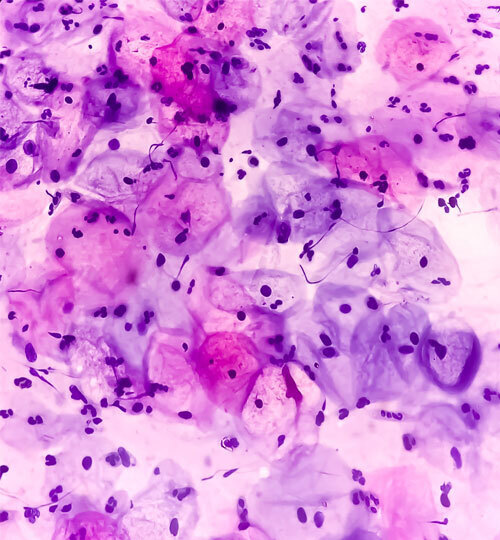

Le suivi de cette étude britannique, plus vaste, couvrait 13,7 millions de personnes-années (âgées de 20 ans à moins de 30 ans en ce qui concerne les cohortes vaccinées). Les données des registres de cancer ont été étudiées entre 2006 et 2019, pour les femmes de 20 à 64 ans, concernant les cancers et les dysplasies intraépithéliales de grade 3 (CIN3) du col utérin. Pendant cette période, 27 946 cancers du col de l’utérus et 318 058 CIN3 ont été diagnostiqués. Pour ces deux pathologies, la diminution du risque relatif atteignait respectivement 87 % et 97 % pour les filles vaccinées entre 12 et 13 ans, 62 % et 75 % entre 14 et 16 ans, et 34 % et 39 % entre 16 et 18 ans, comparées aux cohortes non vaccinées. Ainsi, les auteurs ont estimé qu’en juin 2019, la vaccination anti-HPV avait permis d’éviter 448 cancers du col et 17 235 CIN3 ; autrement dit, que la campagne vaccinale anti-HPV permet la quasi-élimination du cancer du col utérin chez les femmes nées depuis septembre 1995.

Ces travaux fournissent ainsi la première preuve directe de l’effet de la vaccination anti-HPV par un vaccin bivalent sur l’incidence du cancer du col de l’utérus. Des données d’autant plus encourageantes que ce vaccin est depuis remplacé par des vaccins ayant plus de valences (Gardasil 4 et 9).